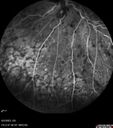

central retinal vein occlusion - a lot of hemorrhage - on coumadin

84 year old man with severe vision loss left eye for 2 weeks. VA 5/200 OS - Patient on Warfarin for valve replacement.

CRVO with Edema - Hemorrhage on Warfarin